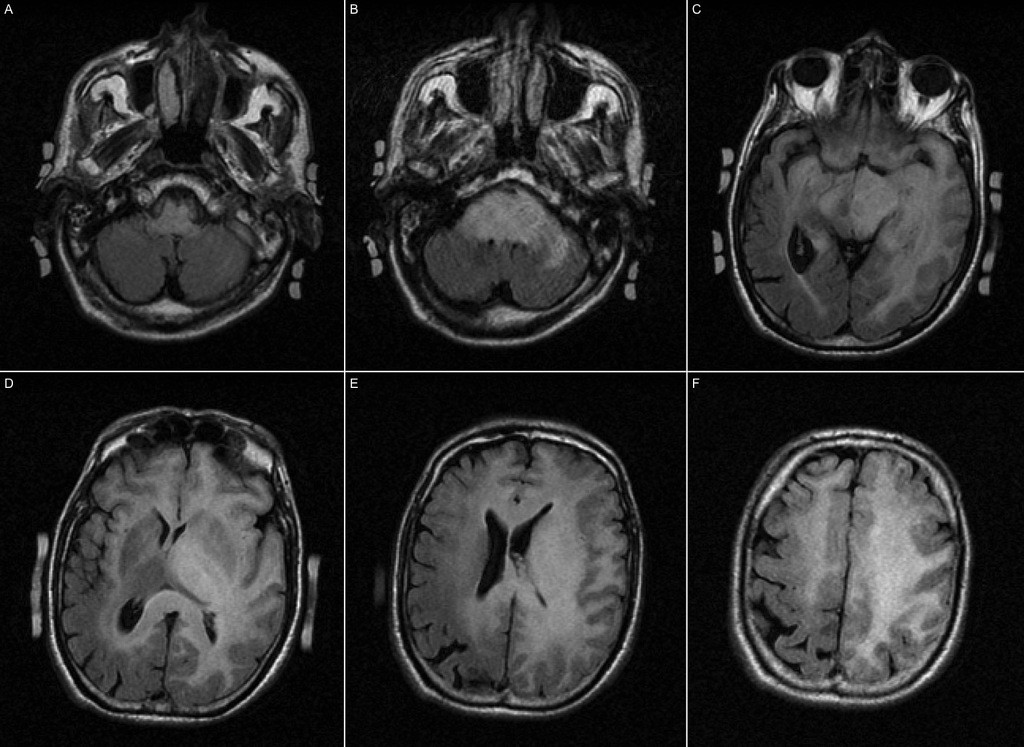

Glioblastome Stade 4 Guérison. Glioblastome Le glioblastome de grade 4, une forme agressive de tumeur cérébrale, représente un défi médical majeur Les patients atteints de cette condition font face à une progression rapide de la maladie, souvent accompagnée de symptômes sévères

Le glioblastome est une tumeur cérébrale de stade 4 c'est-à-dire très agressive qui touche plus souvent les hommes que les femmes, entre 45 et 70 ans Le glioblastome de grade 4, une forme agressive de tumeur cérébrale, représente un défi médical majeur

Glioblastome: espérance de vie, recherches & innovations thérapeutiques De nombreuses molécules et techniques sont en cours d'exploration afin d'augmenter l'arsenal thérapeutique et l'efficacité des traitements de cette maladie agressive. Mon conjoint est atteint d'un Glioblastome stade 4 diagnostiqué en mai 2016, opération avec exérèse totale ou presque (en vérité la totale n'existe pas), suivi du traitement standard (33 séances de radiothérapie + témodal et ensuite cure de Temodal 5 jours/mois). Le glioblastome (GBM) est la tumeur primitive la plus agressive du SNC

Image. Nous avons analysé les caractéristiques des patients ayant une survie prolongée (LS) Le glioblastome de grade 4 reste un défi majeur dans le domaine de la neurologie et de l'oncologie

La glioblastome, qu'estce que c'est. Nous avons revu les dossiers de 127 patients qui ont bénéficié d'une chirurgie pour un GBM entre janvier 2002 et novembre 2011 dans notre centre. Cette maladie complexe représente un défi pour les équipes soignantes, qui s'efforcent d'apporter des réponses adaptées malgré les limites des traitements actuels